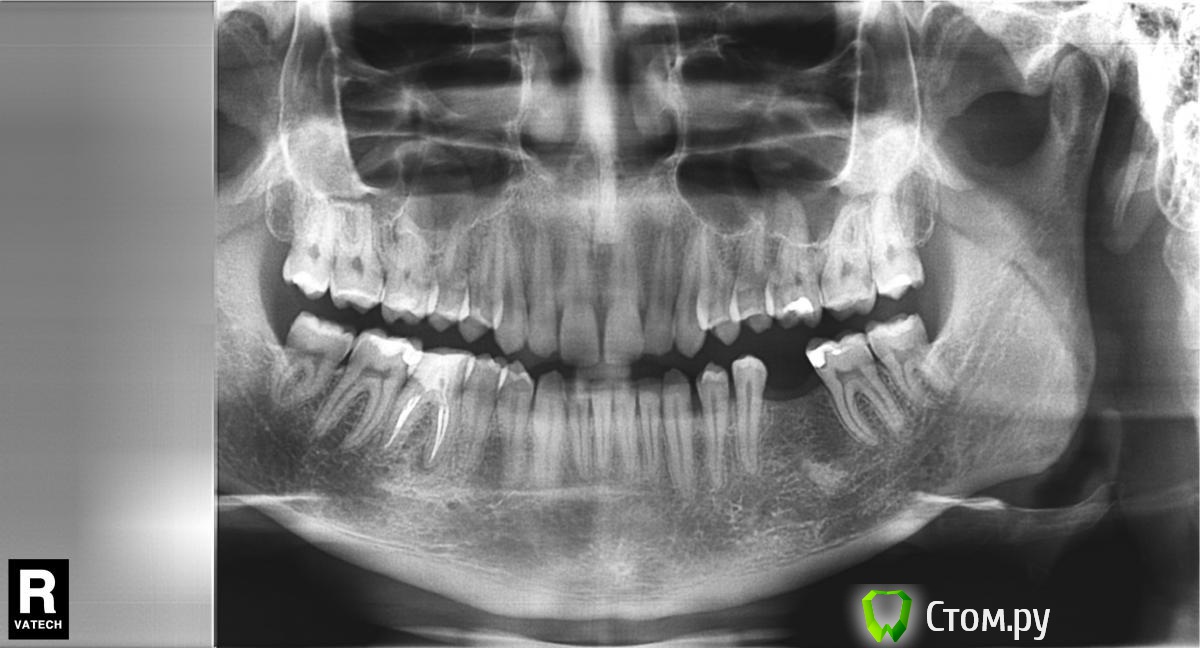

bobrdobr Опубликовано 5 февраля, 2014 Поделиться Опубликовано 5 февраля, 2014 (изменено) Здравствуйте, уважаемые ортопеды! Выбираю вариант восстановления 46 зуба на импланте.Свежий панорамный снимок во вложении.Вот моя хирургическая тема:http://forum.stom.ru/topic/24687-proshu-pomoch-s-vyborom-khirurga-dlia-implantatcii/ Побывал на приеме у ортопеда. Предложены варианты коронок: металлокерамика, безметалловая керамика e-max, цирконий. Настоятельно рекомендуется e-max.Эстетика мне не важна, важна долговечность конструкции. Имплант, судя по всему, будет Bicon. Меня интересует следующее:Изначально настраивался на металлокерамику. Действительно ли технология изготовления металлокерамики не позволяет обеспечить плотное прилегание коронки к абатменту? Есть какие-то недостатки у коронки на e-max? Есть какие-то причины рассматривать цирконий в моем случае? По моей ситуации: 45 зуб некритично сместился в сторону отсутствующего 46. Антагонист 16 некритично опустился вниз. Планируется ограничиться стачиванием выраженного жевательного бугра на антагонисте. Кажется такой план разумным? Каковы преимущества/недостатки имплантов Bicon в части протезирования на жевательных зубах?Ортопед озвучил следующее:+ Абатмент у Bicon, в отличие от винтовых имплантов, имеет выраженную шейку и ее можно дофрезеровать, учитывая размеры основания коронки и особенности десны. У винтовых имплантов абатмент внутри, а на жевательном зубе винт всегда уже чем коронка, поэтому соединение коронка-имплант получается менее анатомичным.- Bicon дает небольшую усадку, поэтому коронка ставится выше на пару мм. Жевать в первое время может быть не очень удобно Если вопросы уже задавались, прошу извинить. Заранее спасибо! Изменено 5 февраля, 2014 пользователем bobrdobr Ссылка на комментарий